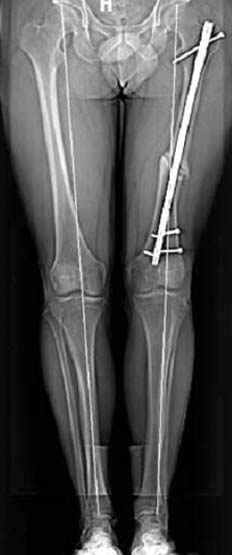

Несколько снимков из моей коллекции, чтобы разьяснить, почему мы до сих пор делаем различные варианты остеотомии.

На рисунке N1 предоперационный план лечения ложного сустава шейки бедра- линия ложного сустава, угол и направление введения импланта, клиновидная остеотомия в градусах и миллиметрах, второй снимок после коррекции, расчет, на сколько удлиняется конечность и размеры импланта;

N3 рисунок окончательный снимок, после операции моя рентгенограмма должен выглядеть примерно как эта картина. На N4 снимке клин перед удалением; N5 послеоперации 3 нед.; N6 окончательная рентгенограмма.

Отправитель: Djoldas Kuldjanov 23 Ноябрь 2004, 18:21

пластическая модель; и коррекция бедра аппаратом Илизарова.